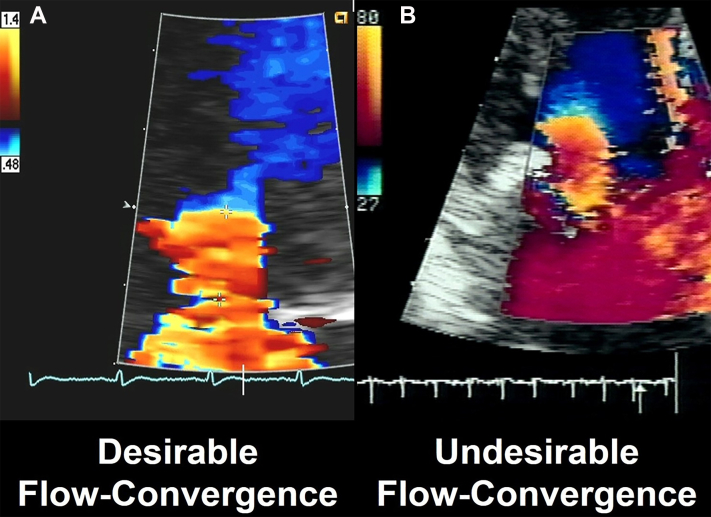

Adjust aliasing velocity to obtain the desired flow convergence shape. The desirable shape is a “ball” sitting on the jet, reflecting a true flow-hemisphere (Figure 1A), the sides of which are progressively lost to visualization toward the 90-degree angle, due to the Doppler effect. With too-high aliasing velocity, the flow convergence appears pancake-like, and with too-low aliasing velocity, it appears like a football or rugby ball (Figure 1B). If the flow convergence shape is irredeemably deformed, reject it (Figure 2). Record long segments of multiple beats to average and reduce measurement variability.

Figure 1.

Imaging Characteristics Affecting the Flow Convergence Assessment

(A) The appearance of the flow convergence in the case of a hemispheric flow convergence. Because color-flow imaging is based on Doppler effect, with an increasing angle vs the beam of ultrasound, the flow display decreases and disappears at 90 degrees. Thus, a hemispheric flow convergence will appear as a “ball sitting on the jet.” Furthermore, this Doppler effect underscores the importance of measuring the radius in the direction of the ultrasound beam. (B) Schematic representation of the effect of the aliasing velocity on the shape of the flow convergence. With too-low aliasing velocity, the flow convergence appears football-like (pale yellow shape) and with too-high aliasing velocity the flow convergence appears pancake-like. Both are inappropriate for measurement, whereas the intense-yellow medium shape is appropriate for measurement.

Figure 2.

Imaging of the Flow Convergence

(A) A desirable flow convergence appropriate for measurement in shape and timing. (B) An undesirable, deformed flow convergence inappropriate for measurement.